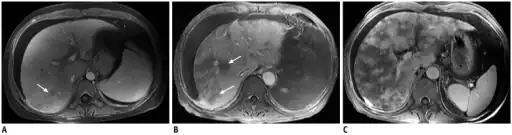

Doppler ultrasound of the liver is typically utilized to confirm or suggest the diagnosis. Common findings on liver doppler ultrasound include increased phasicity of portal veins with eventual development of portal flow reversal. The liver is usually enlarged but maintained normal echogenicity. A liver biopsy is required for a definitive diagnosis.